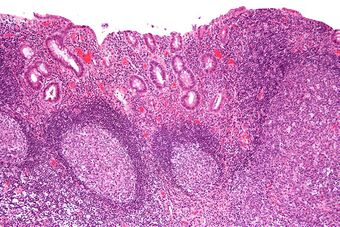

Micrograph showing colonic-type mucosa with follicular lymphoid hyperplasia, as is seen in diversion colitis. H&E stain.

Diversion colitis is an inflammation of the colon which can occur as a complication of ileostomy or colostomy, where symptoms may occur between one month and three years following surgery.[1] It also occurs frequently in a neovagina created by colovaginoplasty, with varying delay after the original procedure.[2] Despite the presence of a variable degree of inflammation the most suggestive histological feature remains the prominent lymphoid aggregates.